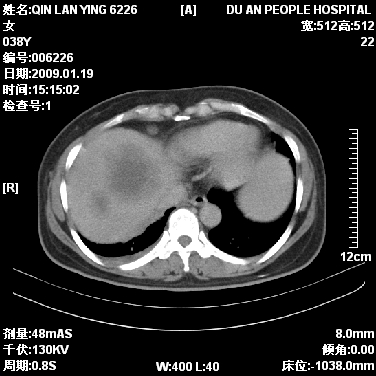

本病例有几个容易诊断的地方:1、右肺上叶前段支气管闭塞,肺不张。2、淋巴结明显肿大。3、肝脏多个类圆形低密度影呈“牛眼征”改变,高度提示转移。

从影像学角度分析      右肺上叶中央型肺癌,并阻塞性不张、肺炎,纵隔淋巴结、膈顶淋巴结转移。

肝内两个大小不等低密度结节,内可见更低密度影,首先考虑肝内转移瘤,但联想到患者wbc1万4,建议楼主还是做个增强比较明确,除外肝脓肿的可能。